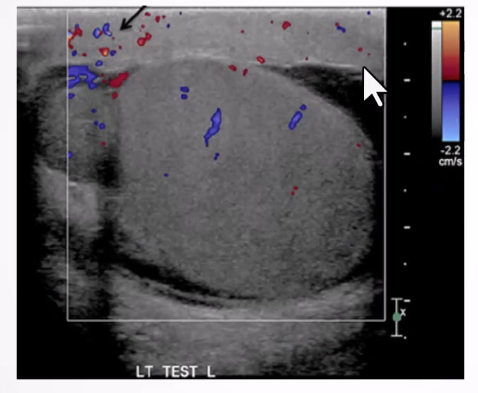

Altered Blood Flow:

Intratesticular arteries characteristically have a low resistance pattern with a mean resistive index of 0.62 (range 0.48 - 0.75)

Incomplete torsion - reversal of distolic flow and RI >0.75

Complete torsion - absence of blood flow in both the testis and epididymis